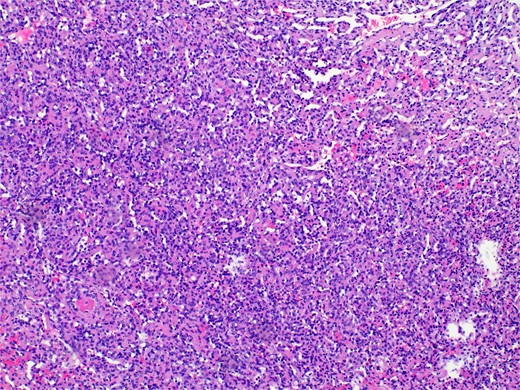

Pathology revealed a benign vascular neoplasm, whose morphological pattern favored AH (Figs 3 and 4).

Histopathology micro findings showing anastomosing proliferation of capillary-sized vessels with mild endothelial cell nuclear variability.

Histopathology micro findings showing scattered “hobnail” cells.